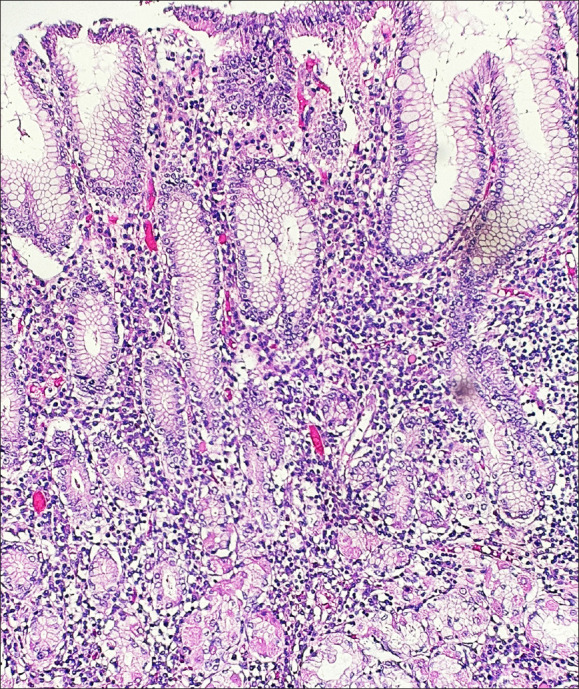

Abstract Image